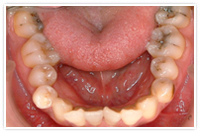

上下の乱杭歯と口元が出ているのを全部矯正で治した症例

治療前

- 上顎前から4番目、下顎前から5番目の歯を抜いて全部矯正にて前歯を内側に引っ込めました。上顎の歯を抜いた場所には目立たないよう仮歯を接着しました。

約22ヶ月で保定へ移行しました。

- 治療期間22ヶ月